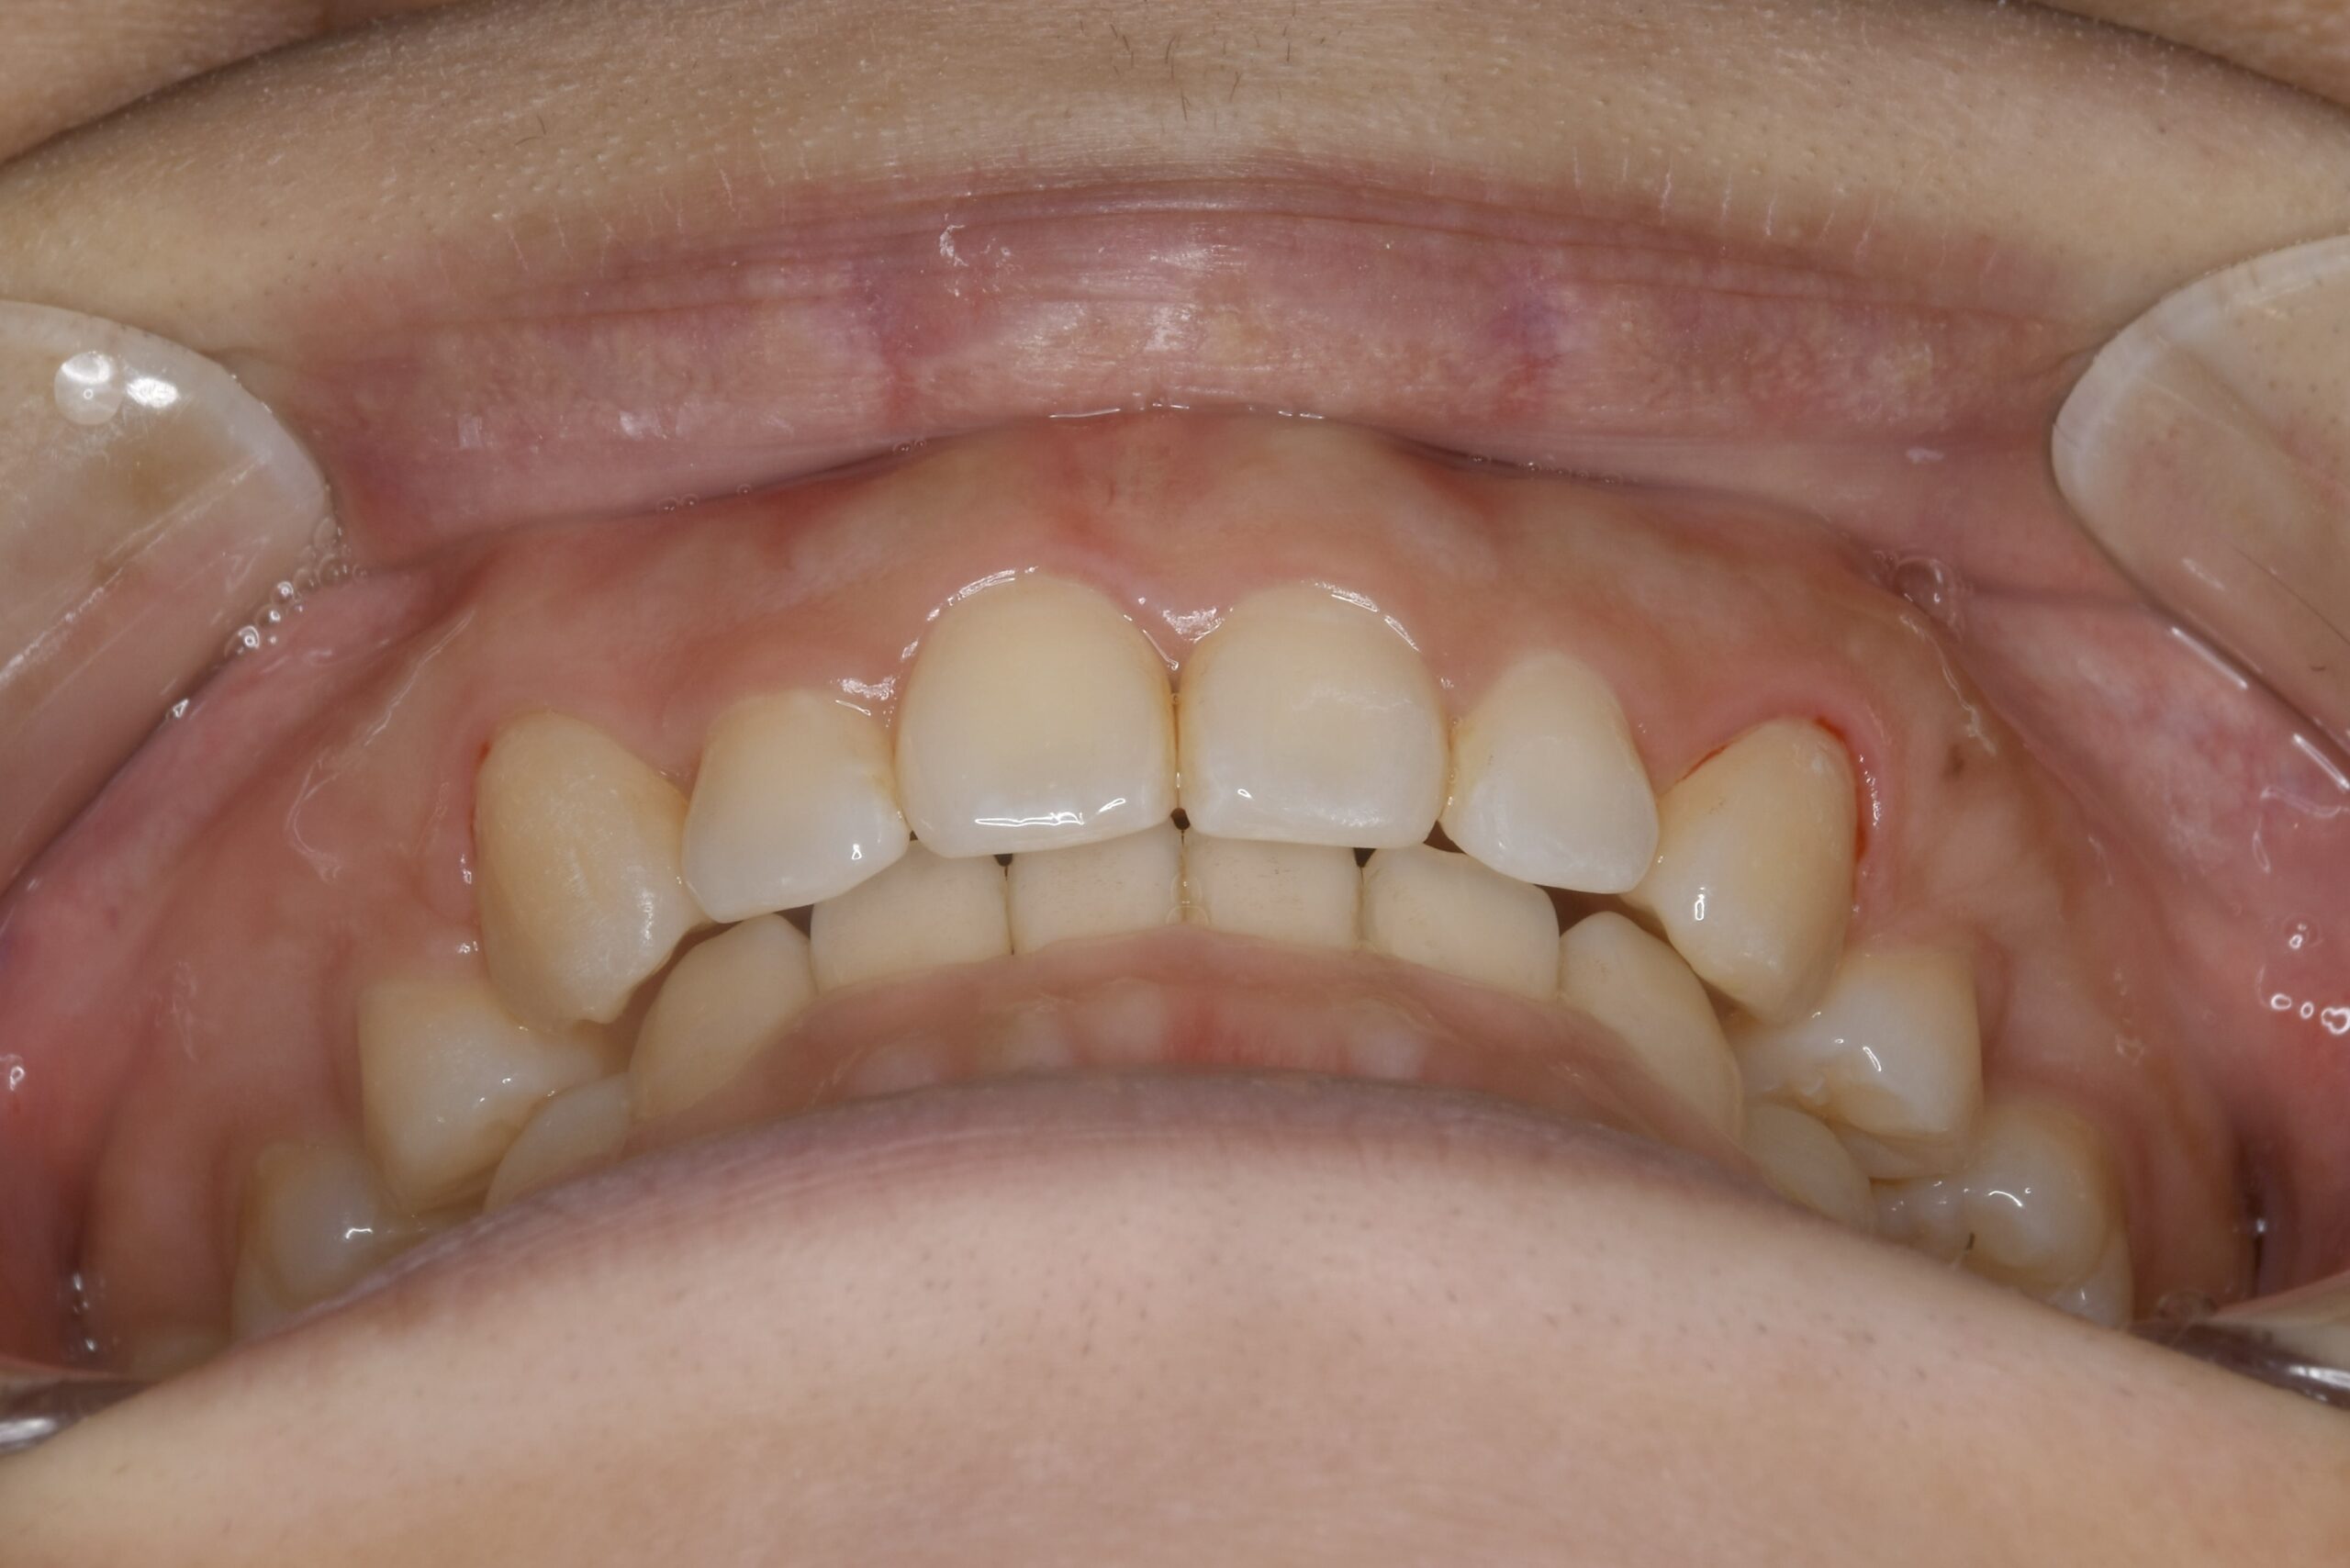

32歳 女性 治療期間:1年7ヶ月

AFTER

主訴 口元が出ていて気になる。

診断名・主な症状 叢生を伴う上顎前突

治療内容 上下とも歯を2本抜いて、上の前歯を後方に引きながら、でこぼこを治しました。

使用装置 マウスピース矯正装置(インビザライン)

抜歯部位 上 両側4番目

下 右側4番目、左側5番目